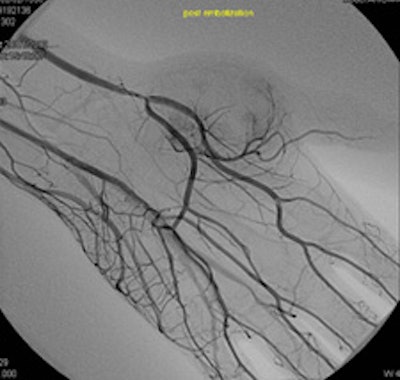

Bilbao and his colleagues are shown in the angiography suite at Clínica Universidad de Navarra.How are Spain's well-documented economic difficulties affecting you?